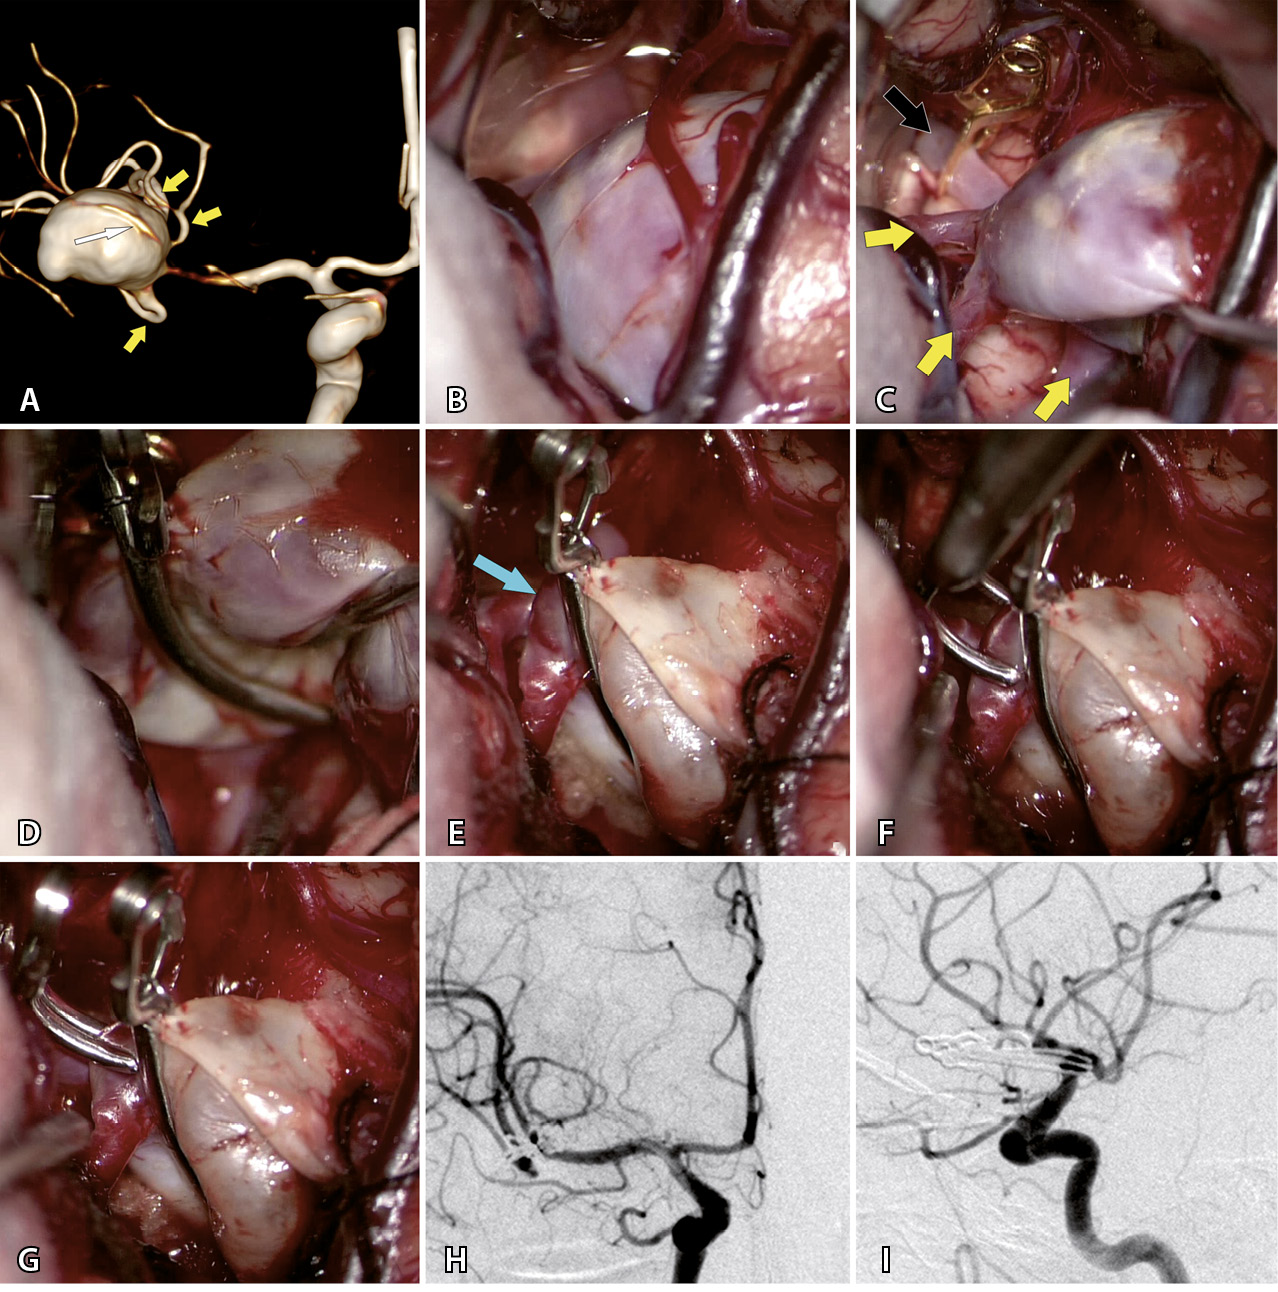

Наиболее частой операцией было клипирование шейки (КШ) – в половине (50,9%) всех случаев. Клипирование аневризмы одной клипсой произведено только в 5 наблюдениях. У остальных 23 пациентов выполнено множественное клипирование с наложением от 2 до 7 клипс (в среднем – 3,2 ± 1,5). Пример клипирования гигантской аневризмы приведен на рис. 1. У 17 больных перед КШ проведена тромбэктомия из полости гигантской аневризмы. У 6 больных тромбэктомию делали после КШ.

Рис. 1. Клипирование гигантской аневризмы средней мозговой артерии (СМА) справа у пациентки Г., 59 л. А – при компьютерной томографической ангиографии определяется гигантская аневризма трифуркации СМА справа (желтыми стрелками указаны три М2-ветви СМА справа, белой стрелкой указана припаянная к телу аневризмы передняя височная артерия). Б – интраоперационное фото: отмечается выступающее в сильвиеву щель тело аневризмы СМА справа. В – после наложения временной клипсы на М1-сегмент справа (указан черной стрелкой) мешок аневризмы релаксировал, что позволило выделить и визуализировать три М2-ветви (указаны желтыми стрелками). Г – длинная изогнутая клипса наложена на шейку аневризмы. Д – после клипирования наблюдается небольшой остаточный участок шейки аневризмы (указан стрелкой) у теменного М2-сегмента. Е – наложение на остаточный участок шейки аневризмы маленькой изогнутой клипсы. Ж – результат клипирования шейки аневризмы двумя клипсами. З – контрольная церебральная ангиография в прямой проекции. И – контрольная церебральная ангиография в боковой проекции